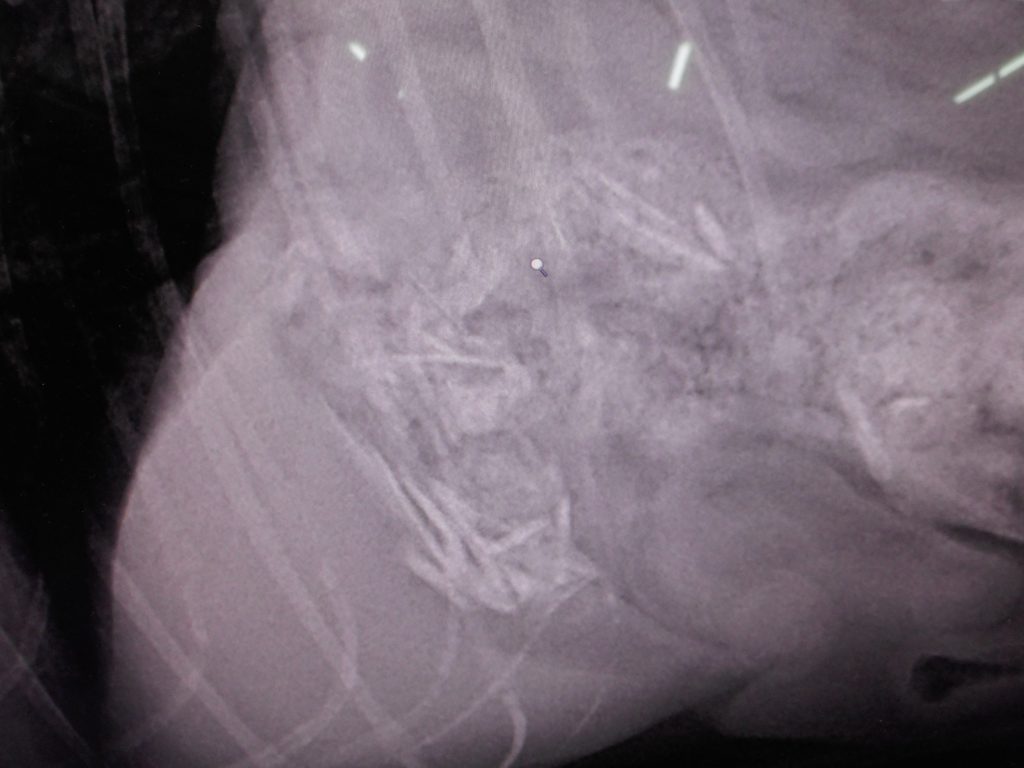

どこにあるか?

ココです

骨ごといってます